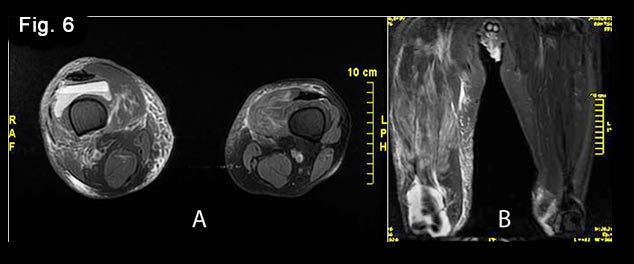

Figure 2:Longitudinal views of the left-sided thigh

A. Panoramic view of the vastus medialis muscle showing swelling of the distal part of the belly with focal irregularities and changes of the echogenicity pattern (arrow).

B. Longitudinal grayscale image peripherally to Fig. A showing a small quantity of fluid within the left suprapatellar recess (arrow).